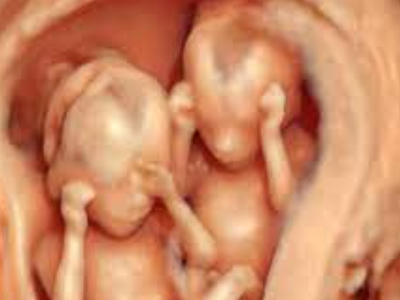

Imagen 1er. Trimestre

Ultrasonido estructural de 1er. trimestre

Diagnóstico en la identificación de defectos estructurales potencialmente detectables.